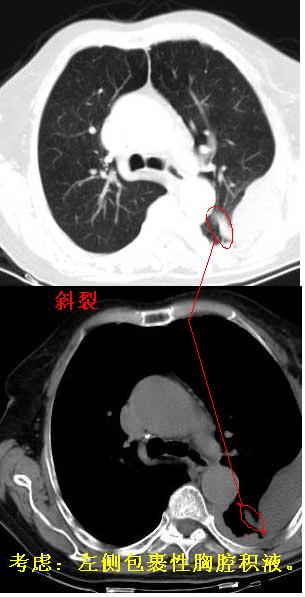

标题: CT0563:病历讨论,胸膜间皮瘤? [打印本页]

标题: CT0563:病历讨论,胸膜间皮瘤?

测ct值3-6hu,

既然ct值是3-6hu,还不如考虑包裹性积液。

支持包裹性胸腔积液。

请上传纵隔窗。目前还是支技包裹性积液(明显梭形),即使是间皮瘤并积液也少梭形的。

从图片看,包裹性积液好象更合理,梭形,ct值3-5hu(在哪看到的?);胸膜间皮瘤如此规则,不多见。

左侧背部胸膜肥厚,伴包裹性积液,不考虑间皮瘤.

同意以上各位的高见,首先考虑包裹性积液,1.胸膜间皮瘤积液量一般较大,以游离性积液更为常见,2.可以看到增厚的胸膜结节